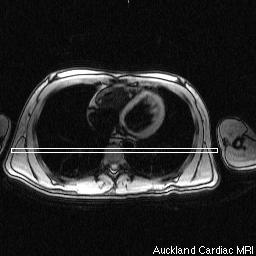

This project seeks to establish a structural and functional atlas of the heart. Initially comprising cardiac magnetic resonance imaging (MRI) examinations, together with derived functional analyses and associated clinical variables, the database will be extendible to allow inclusion of data from a variety of imaging and other sources. Cardiac MRI examinations provide detailed, quantitative data on heart structure and function, and standardized protocols are now routinely used in a number of studies. The initial goals of this project are to facilitate statistical analysis of regional heart shape and wall motion characteristics, across population groups, via the application of parametric mathematical modeling tools. This project will combine cardiac modeling and biophysical analysis methods developed by the University of Auckland with structural database and probabilistic mapping infrastructure developed by the UCLA Center for Computational Biology (CCB). This project is part of the National Centers for Biological Computing (NCBC) collaboration program and is funded by the National Institutes of Health, USA. The specific aims of the project are to: